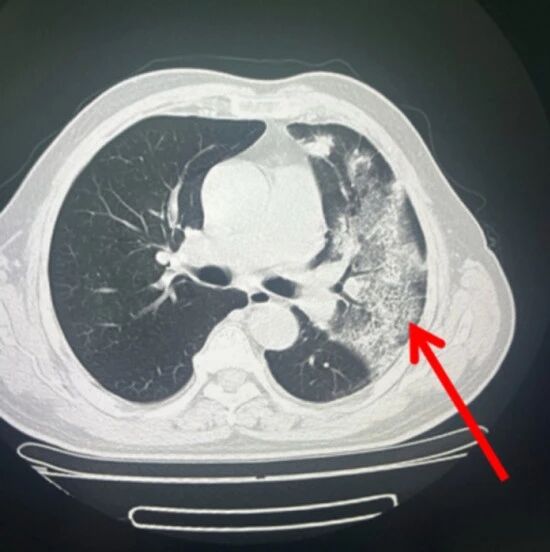

NEJM麻省总医院病例:双肺十余个空洞性结节及肿块,咳嗽发热、右眼一夜失明……致命感染因何迅速经血行...